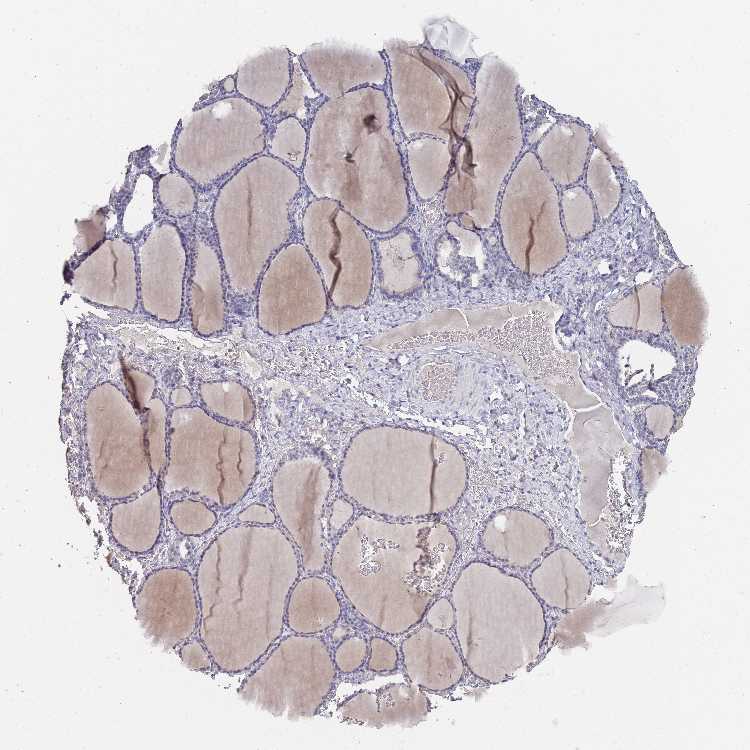

THYROID GLAND - Antibody stainingi

Antibody staining in the annotated cell types in the current human tissue is reported as not detected, low, medium, or high, based on conventional immunohistochemistry profiling in selected tissues. This score is based on the combination of the staining intensity and fraction of stained cells.

Each image is clickable and will lead to virtual microscopy that enables deeper exploration of all samples and also displays staining intensity scores, fraction scores and subcellular localization as well as patient and tissue information for each sample.

Antibody HPA049325

Glandular cells Low